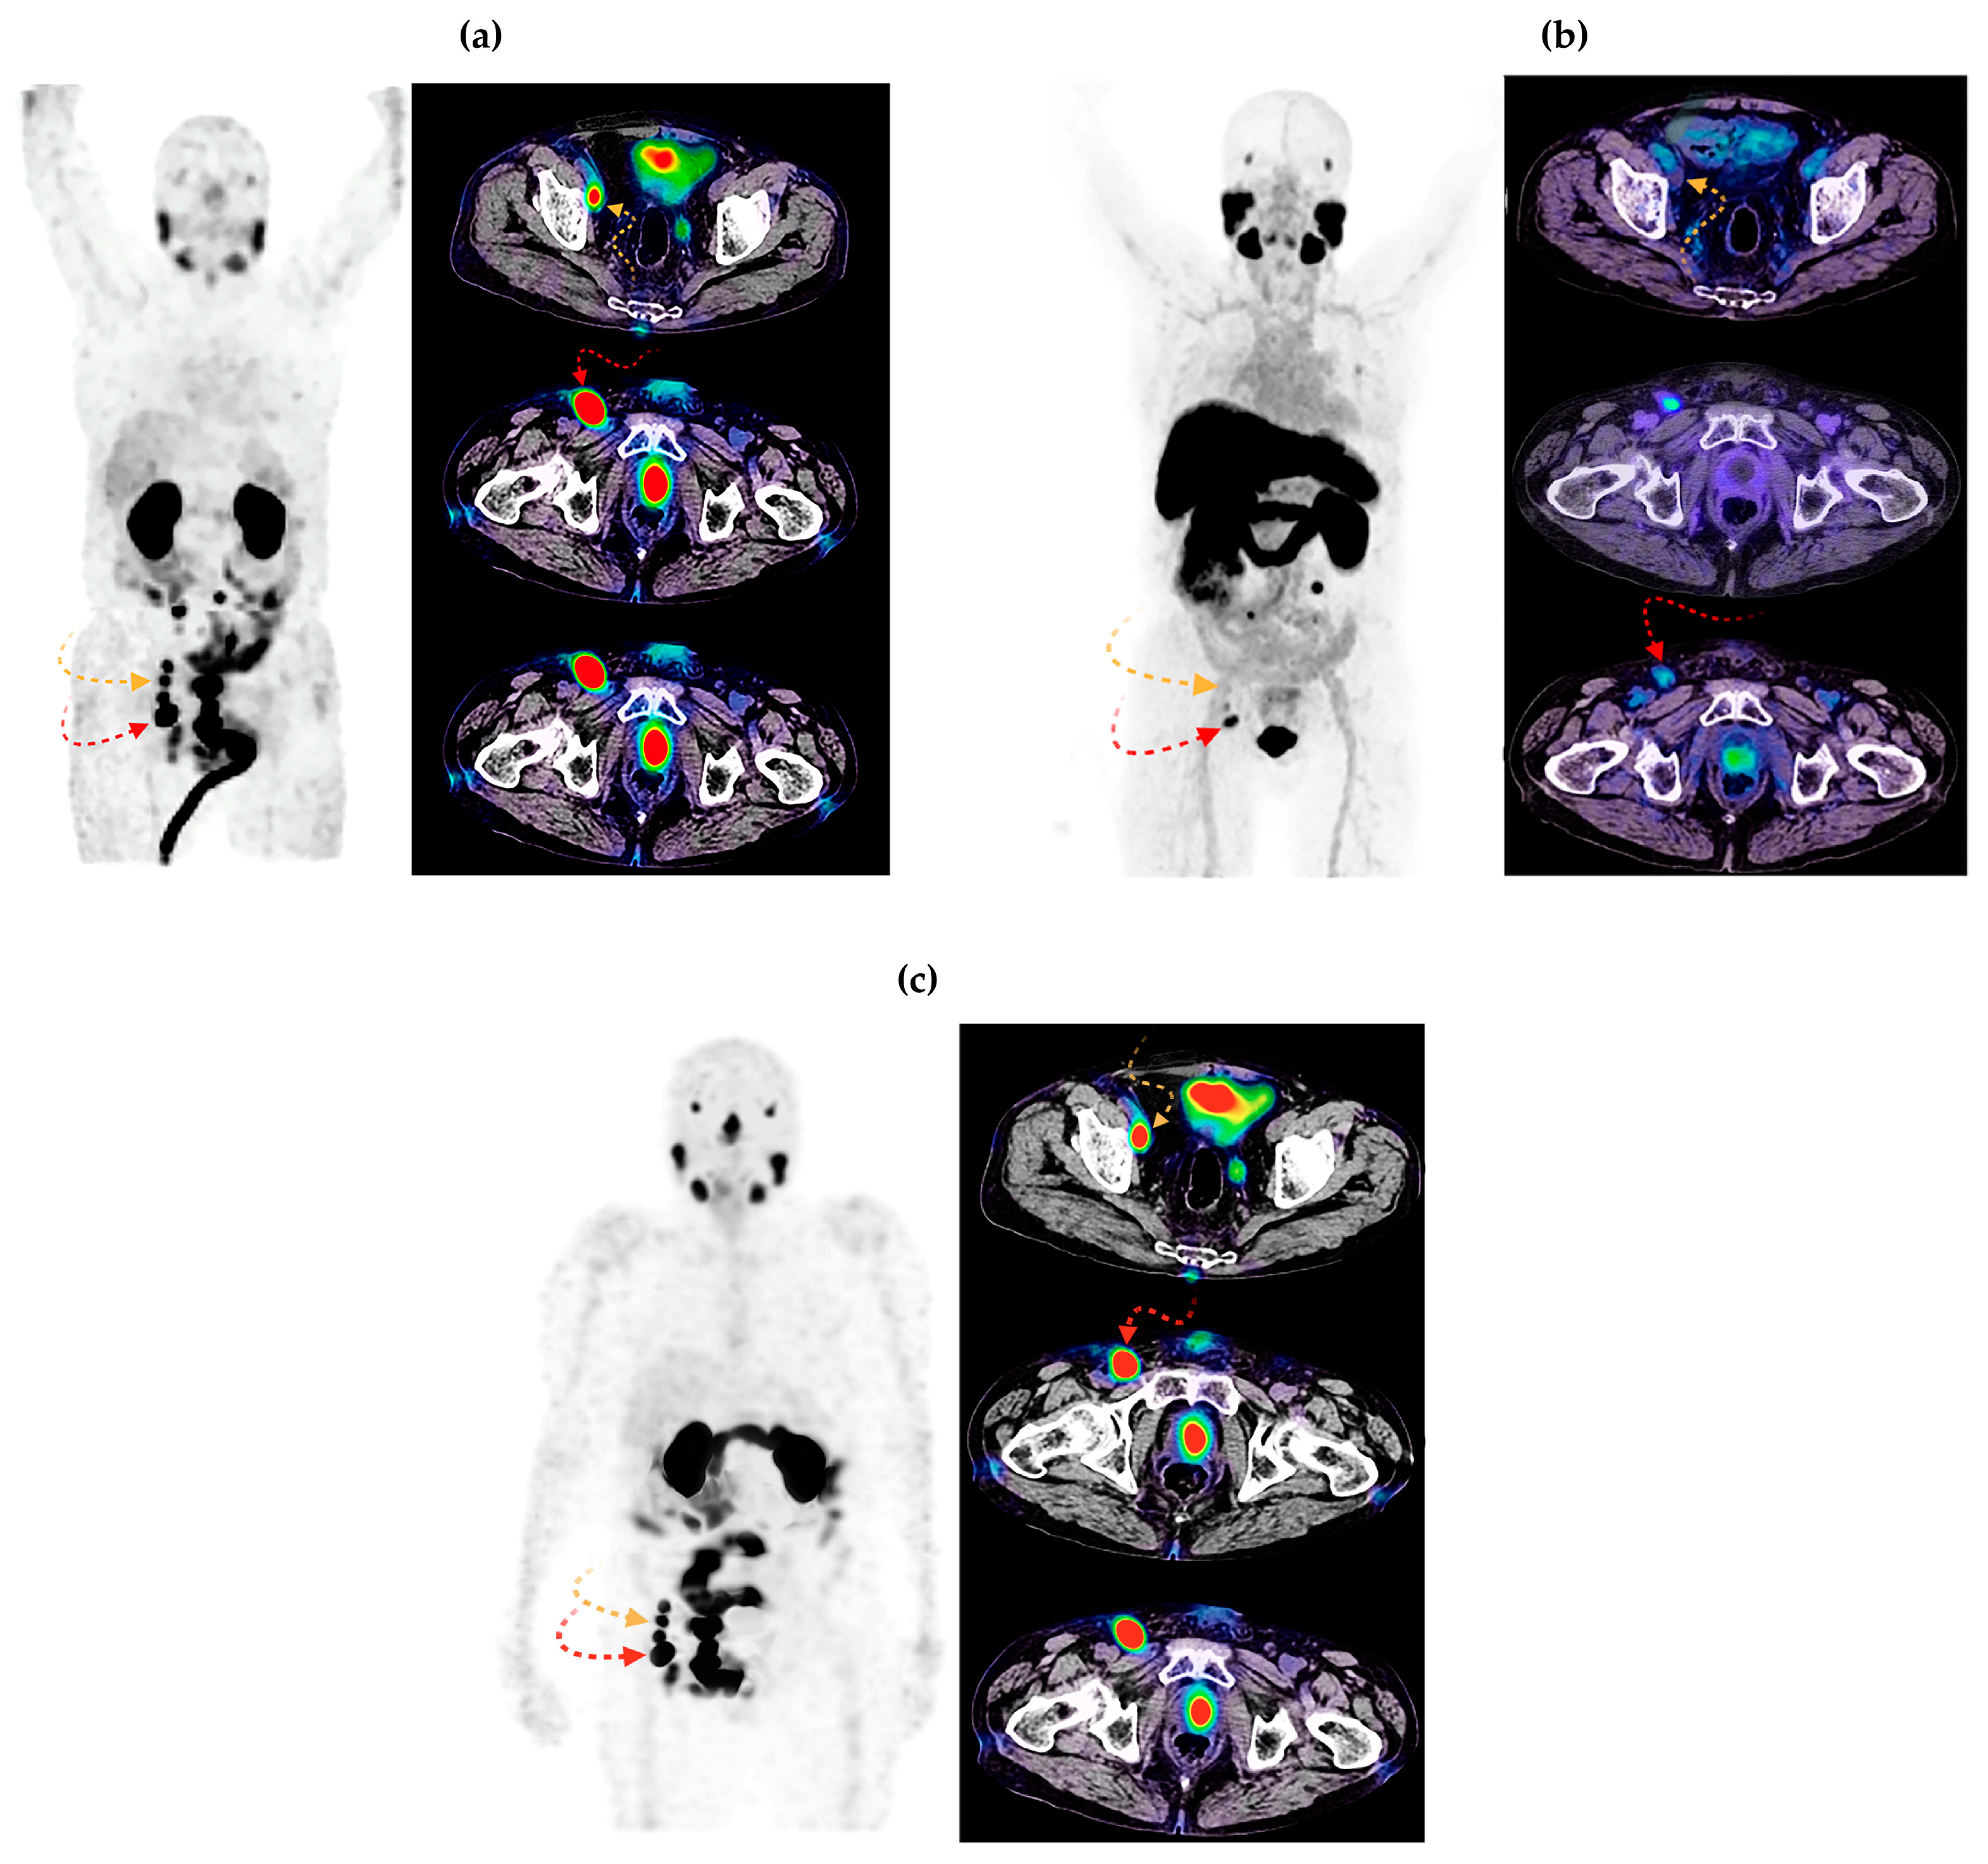

3.2.2. Imaging in Patients